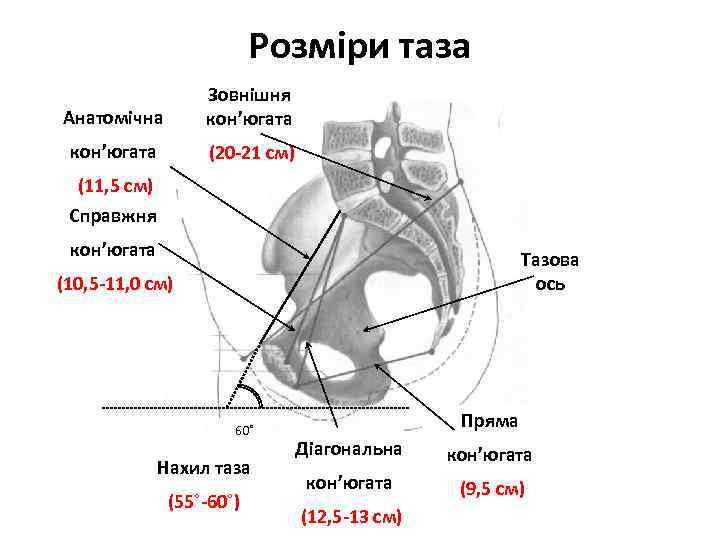

Розміри таза Анатомічна Зовнішня кон’югата (20 -21 см) (11, 5 см) Справжня кон’югата Тазова ось (10, 5 -11, 0 см) 60˚ Нахил таза (55˚-60˚) Пряма Діагональна кон’югата (9, 5 см) (12, 5 -13 см)